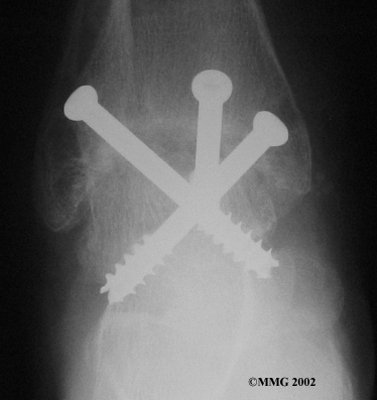

It is important when the surfaces are removed that the angles of the cut surfaces are correct. When the tibia is brought against the talus, the foot should be at a right angle to the lower leg. Once the cuts are made the bones must be held in place while they fuse. This can be done using large metal screws and metal plates if necessary. The screws are usually under the skin and are not removed unless they begin to rub and cause pain.

Inserting the screws

Using the arthroscope to watch, other instruments are inserted into the ankle joint to remove the cartilage surface. The cartilage surface is removed using a small rotary cutting tool. Once the surfaces are prepared, screws are placed through small incisions in the skin to hold the bones together as they heal, or fuse. This procedure is not significantly different from the open procedure except that the incisions are smaller.